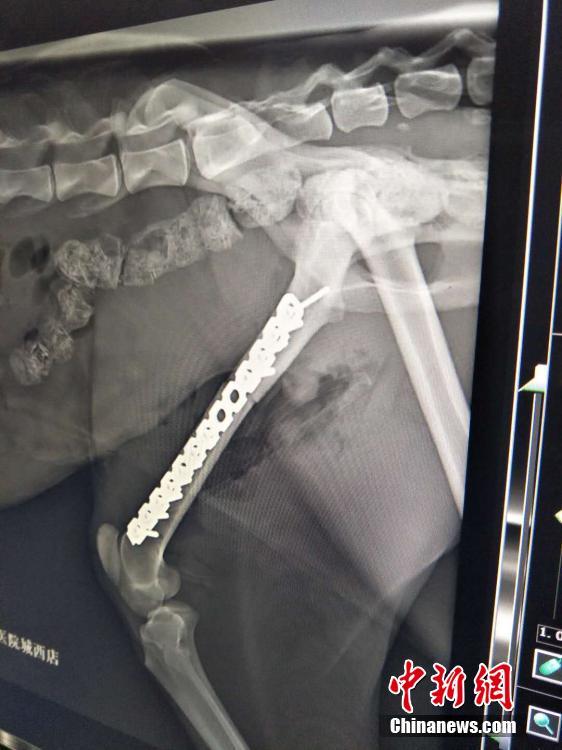

齐新章介绍,15点07分,断骨创面修复吻合后开始加装钢板固定。此次手术受伤雪豹的左后肢打入11枚钢钉,植入16厘米钢板。16点45分钢板加装完毕开始缝合;至17点15分缝合完毕撤离呼吸机,雪豹苏醒,全部手术过程持续3个多小时。张虎 摄